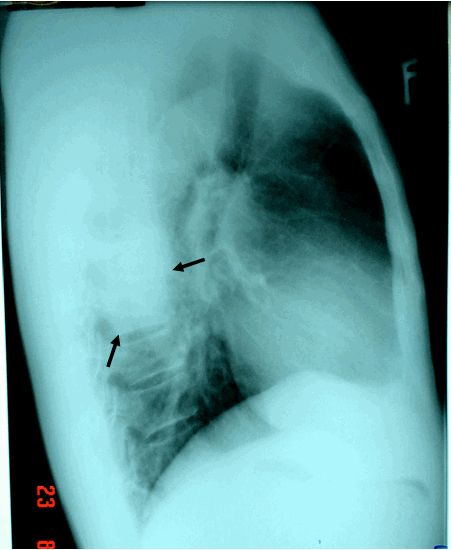

Ung thư phổi thể ngoại vi

Đại đa số các khối u ung thư phổi. Phổ biến nhất, nó phát sinh từ các pseudo-phân tầng biểu mô niêm mạc của đường hô hấp phế quản nhưng cũng có thể phát sinh từ các biểu mô cuối đường hô hấp nhỏ và phế nang. Trên thế giới, ung thư phổi là nguyên nhân phổ biến nhất gây tử vong liên quan ung thư.